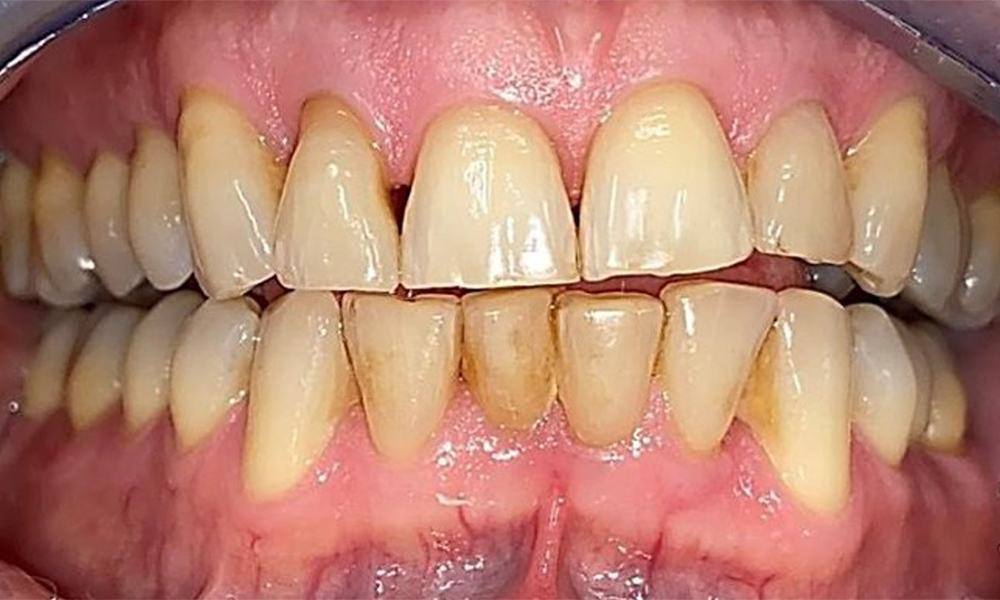

Right lateral view. Loss of the interdental papillae.

Fig. 3 Right lateral view. Loss of the interdental papillae. © Dr R. Krapf

The patient has a full dentition with 28 teeth, which includes amalgam and composite fillings in the molar and premolar regions. There is a visible clinical marginal gap present on tooth 14. Tooth 27 has an adequate gold inlay. There are also generalized attritions and abrasions. (Fig. 2, Fig. 3, Fig. 4, Fig. 5, Fig. 6)

Periodontal findings

The patient has stage II, grade B periodontitis (5). At 1 to 3 mm, the clinical probing depths were within the physiological range. Localized probing depths of 5 mm were observed on the mesiopalatal aspects on both 17 and 27. There are generalized recessions of 1–3 mm with partial loss of the interdental papillae (Fig. 2, Fig. 3, Fig. 4)